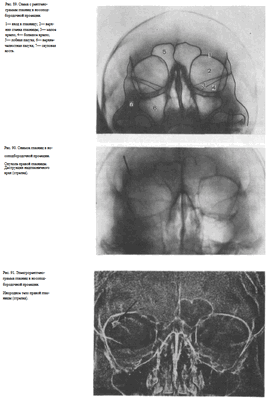

СНИМОК ГЛАЗНИЦЫ В НОСОЛОБНОЙ ПРОЕКЦИИ

Назначение снимка — изучение контуров костей, образующих вход в глазницу, структуры верхней и наружной ее стенок, ширины и контуров верхних глазничных щелей, а также выявление инородных тел в полости глазницы.

Укладка больного для выполнения снимка, информативность снимка, критерии правильности технических условий съемки и правильности укладки те же, что для снимка крыльев клиновидной кости и верхних глазничных щелей.

В качестве примера информативности снимка глазниц в носолобной проекции для выявления инородных тел глаза и деструктивных изменений стенок приводим два наблюдения.

Одно из них — случай ранения глаза металлической стружкой (рис. 93), другое — случай деструкции верхненаружного края глазницы при доброкачественной опухоли слезной железы (рис. 94).